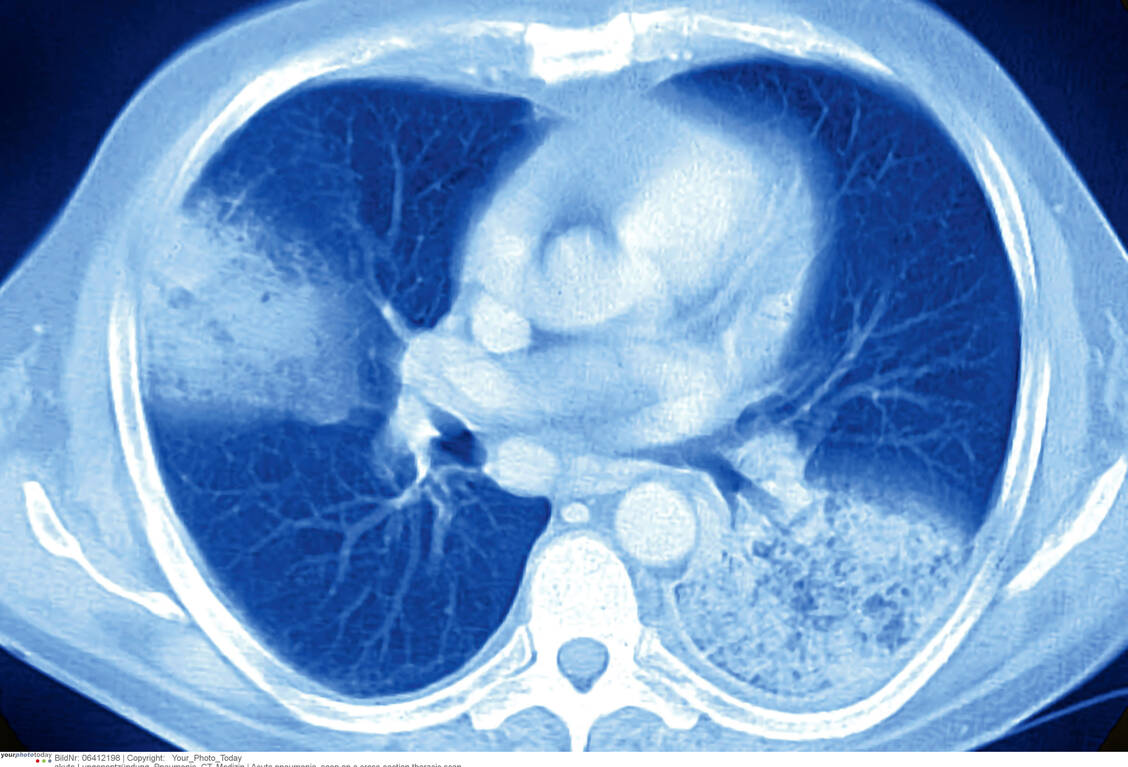

Das Computertomogramm zeigt eine akute Pneumonie beidseits mit schmalem Pleura-Erguss links. / Foto: Your Photo Today

Schon bei begründetem Verdacht auf eine HAP muss unverzüglich eine thorakale Computertomografie (CT) und mikrobiologische Diagnostik erfolgen. Zum Erregernachweis werden auch invasive Probenentnahmen, zum Beispiel Punktionen und Bronchoskopie, und aufwendigere mikrobiologische Techniken, zum Beispiel ein DNA-Nachweis, eingesetzt. Die kalkulierte Antibiotikatherapie beginnt sofort nach der Bildgebung. Dennoch ist die Letalität mit bis zu 17 Prozent aller HAP-Fälle hoch.